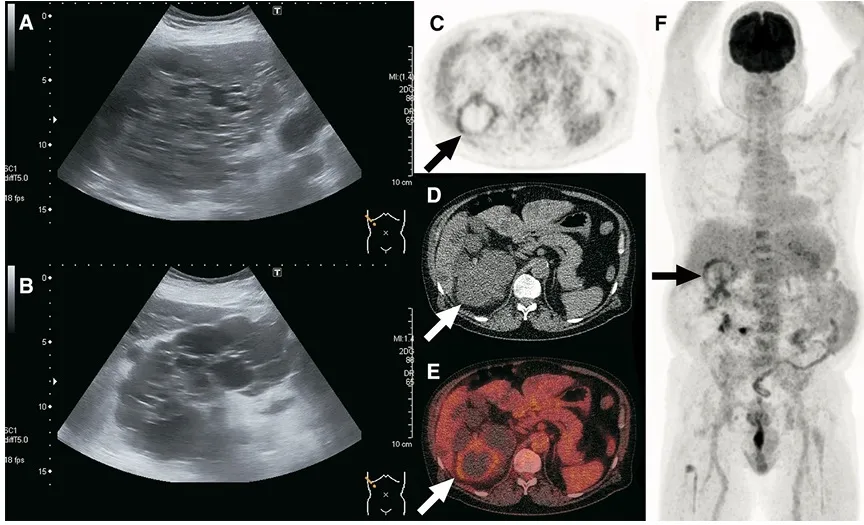

📚 Na série de casos da imagem abaixo (**[link](https://link.springer.com/article/10.1007/s40336-017-0261-8)**), é possível ver como o PET/CT-FDG orienta a conduta e modifica o manejo em infecções renais e hepáticas na DRPAD.

O 18F-FDG PET/CT surge como ferramenta de maior especificidade, útil para localizar o(s) cisto(s) infectado(s) e definir o alvo da punção.

Entretanto, a KDIGO ressalta que o PET/CT não deve ser exame de rotina, devendo ser reservado para casos selecionados, quando os métodos convencionais não esclarecem o diagnóstico.

TC ou RM com contraste podem identificar novo cisto complexo, mas geralmente não diferenciam sangue de pus no interior do cisto.

Achados como realce de parede, espessamento, gás intralesional ou alterações inflamatórias pericísticas aumentam a probabilidade de infecção.